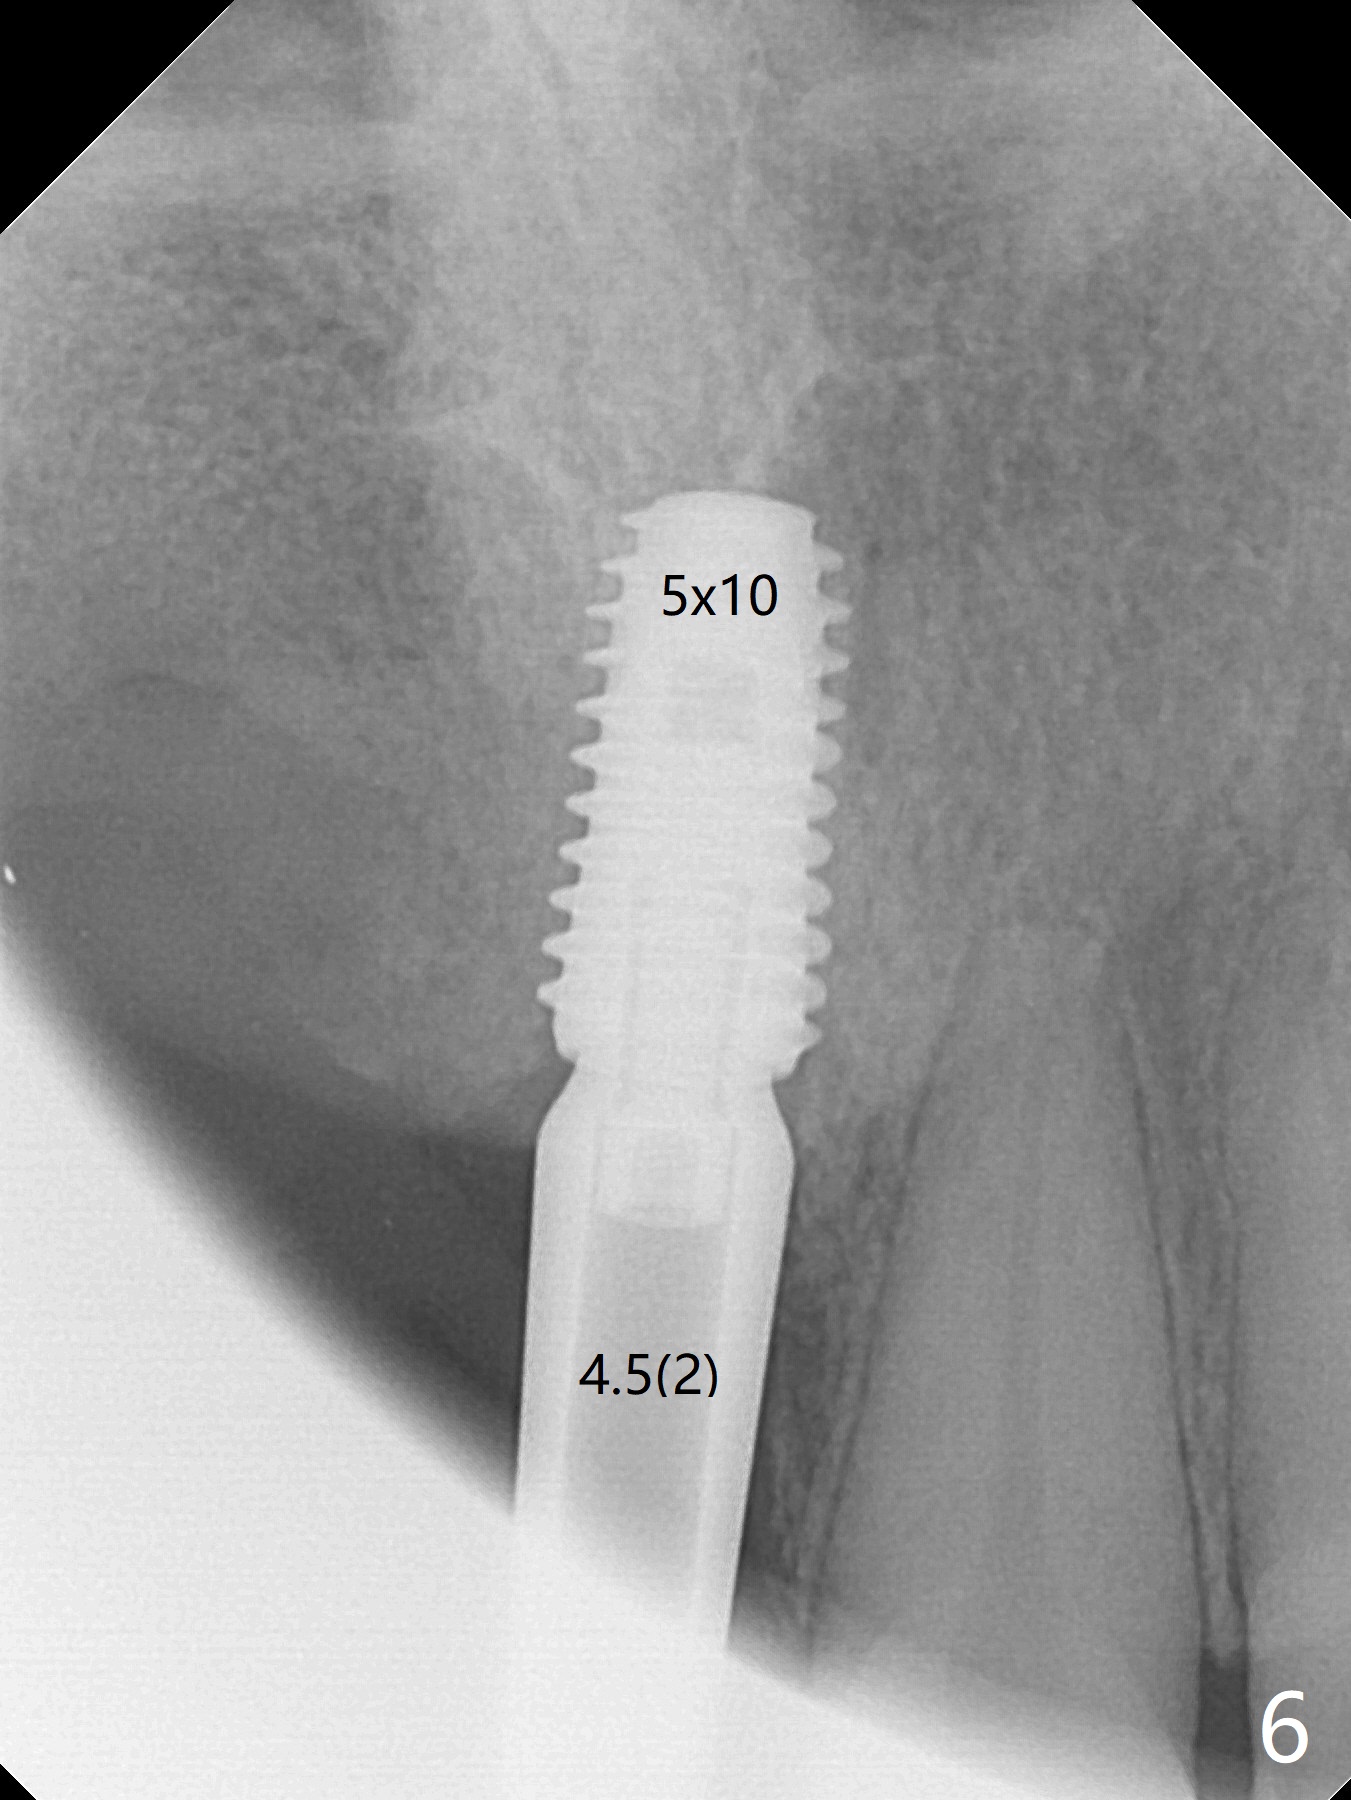

Eleven months post immediate implantation, the implant at #8 (4.5x16 mm, better smaller) is found to have thread exposure buccally (Fig.1) and distally (Fig.2). Immediately post implant removal, a 5x10 mm one is placed equi- or subcrestally distobuccally (Fig.3,4 (to prevent periimplantitis)). It is turned 4 more times later to make sure slightly supracrestally palatally, since the palatal crest is the lowest. After placement of sticky bone palatally, a 4.5(2) mm mill abutment is placed (17 mm long, Fig.5,6). The buccal flap is raised until the anterior nasal (Fig.5 N) foramen. After severing the periosteum and placement of 2 of 8 mm tenting screws (Fig.7), sticky bone (Vanilla allograft/Osteogen; block graft denies) is applied at #6 and 7 sites (Fig.8). Following palatal flap separation, the wound is closed in an apparent tension free manner (Fig.9). Periodontal dressing is applied. After wound healing, lab-fabricated provisional is delivered.